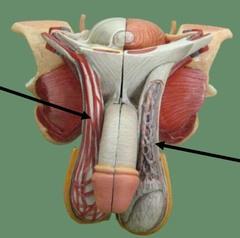

Bulbourethral gland (male)

Corpora cavernosa (pl.) Corpus Cavernosum (s.)

Corpus Spongiosum

Cremaster muscle

Ejaculatory Duct

Epididymis

Prostate gland

Prostatic/spongy urethra (males)

Scrotum

Seminal vesicle

Seminiferous tubule

Spermatic cord

Testis (s.) Testes (pl.)

Vas deferens (=ductus deferens)